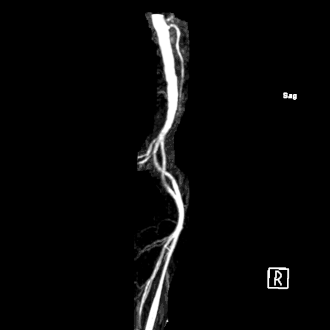

L'artère d'Adamkiewicz est une artère amenant du sang oxygéné vers la moelle spinale. Elle est nommée d'après Albert Adamkiewicz. D'autres dénominations de cette artère sont rencontrées : artère du renflement lombaire, artère radiculaire lombaire, grande artère radiculaire antérieure, artère spinale lombaire, artère de l'intumescence lombale.

Cette artère a des origines variables. Elle se situe le plus souvent à gauche (80 % des cas) et naît généralement de la 9e à la 12e artère intercostale postérieure (70 % des cas) ou de la branche postérieure des artères lombaires[1].

L'artère d'Adamkiewicz irrigue la moelle spinale au niveau de son renflement lombaire, c'est-à-dire au niveau des myélomères lombaires et sacrés. Elle s'anastomose avec l'artère spinale antérieure.